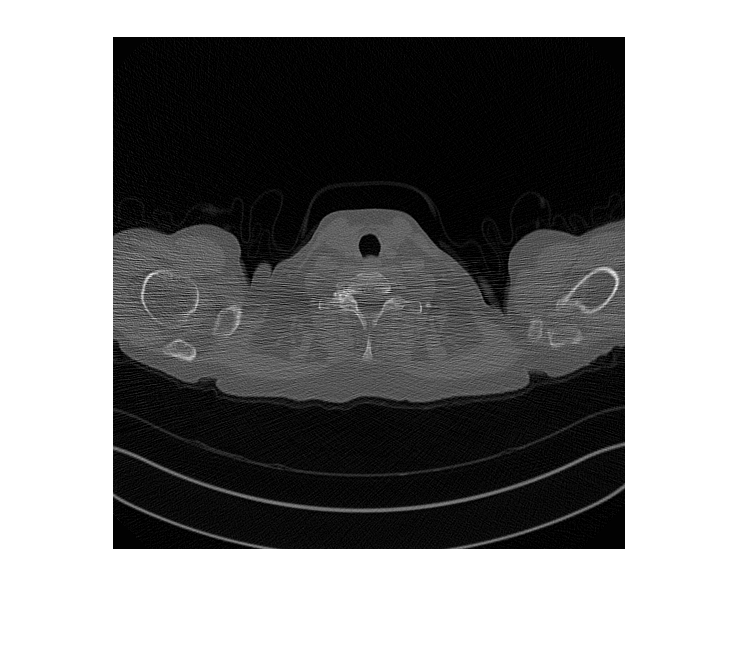

FileExtensions=exts,ReadFcn=readFcn);Предварительно просмотрите учебное изображение от низкой дозы и обучающих наборов данных CT большей дозы.

montage({lowDose,highDose})

Отобразите входной CT низкой дозы, сгенерированную версию большей дозы и изображение большей дозы основной истины в монтаже. Несмотря на то, что сеть обучена на данных из одного терпеливого скана, сеть делает вывод хорошо, чтобы протестировать изображения от других терпеливых сканов.

imshow([imLowDoseTest imHighDoseGenerated imHighDoseGroundTruth]) title(['Low-dose Test Image ',num2str(idxToTest),' with Generated High-dose Image and Ground Truth High-dose Image'])